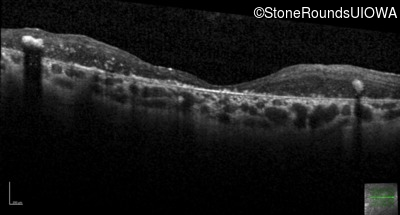

Optical Coherence Tomography - Left - 20/250 sc

Exemplar / OCT Stack